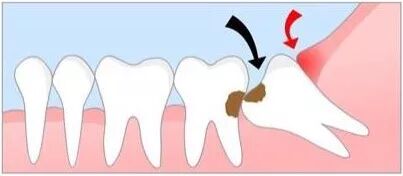

1、阻生智齿

阻生齿是指因为生长的位置不当,导致不能萌出到正常咬合位置的牙齿。因此阻生智齿,通俗点来说,就是“阻碍生长的智齿”,是指因为软组织问题或颌骨骨量不足,智齿不能正常萌出,被牙龈或牙槽骨包裹在里面,经常引发炎症、疼痛。

一般我们说牙疼拔智齿,很多就是阻生智齿,因为大部分甚至全部都埋伏在颌骨中,拔除的难度也比较大,需要削掉一部分颌骨,再将智齿切碎取出,如下图: